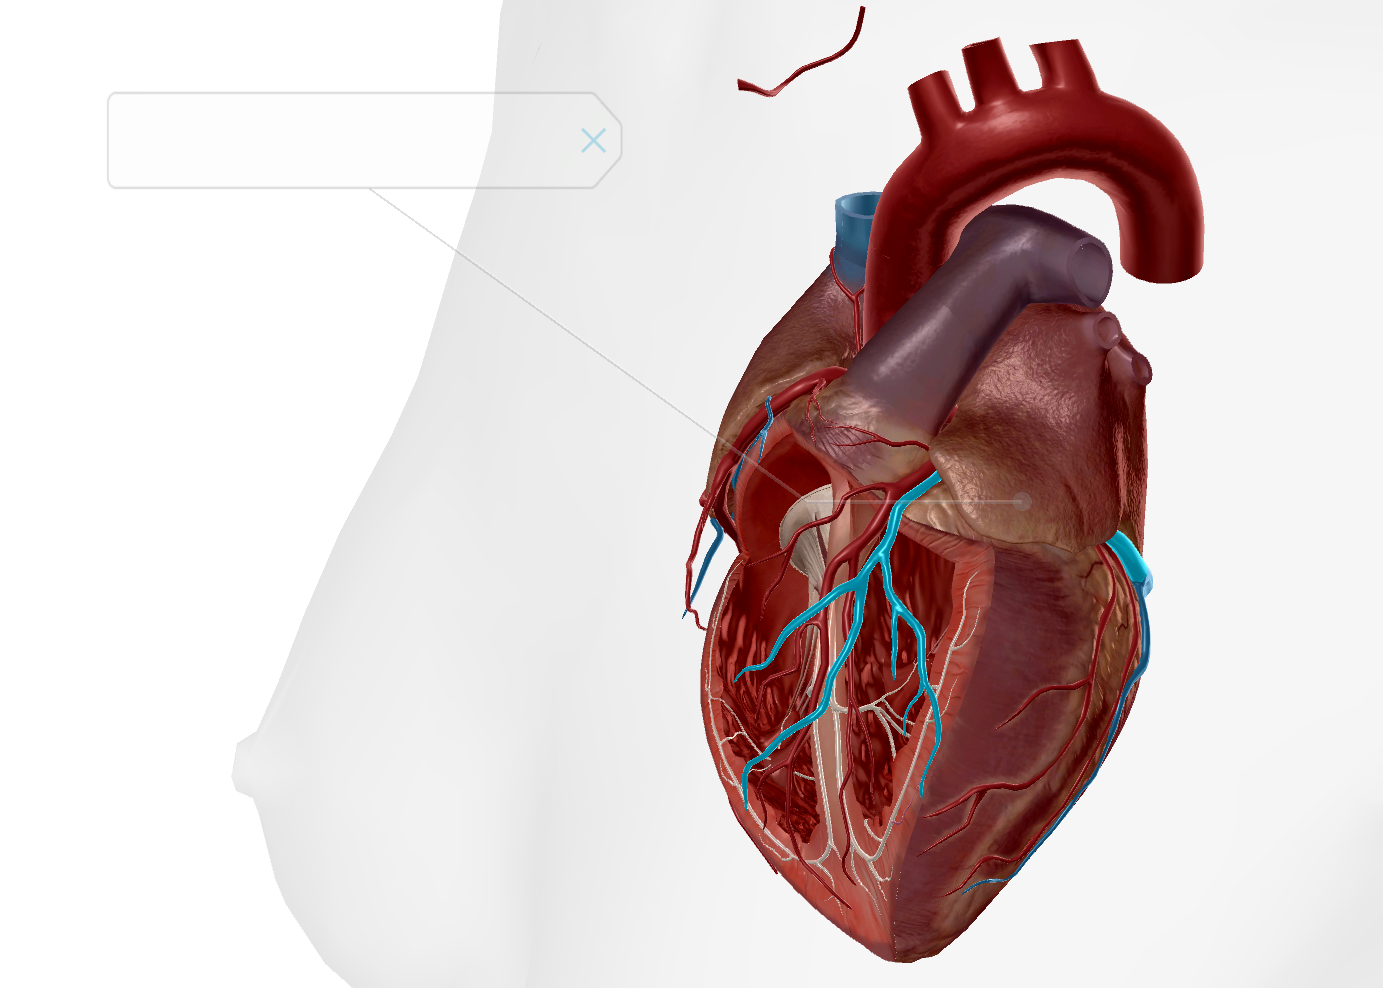

Left Atrium

Right Atrium

Left Ventricle

Right Ventricle

Tricuspid Valve

Bicuspid Valve

Aortic Valve

Papillary Muscle

Pulmonary Valve

Interventricular Septum

Chordae Tendineae

Inferior Vena Cava

Superior Vena Cava

Pulmonary Trunk

Anterior Interventricular Artery

Circumflex Branch

Coronary Artery

AV Node

SA Node

Bundle of His